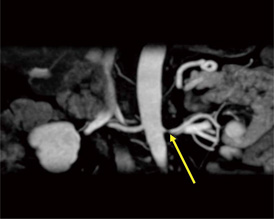

図4 LAVA-XV画像(動脈相)のリフォーマット

腎動脈の狭窄が確認できる。